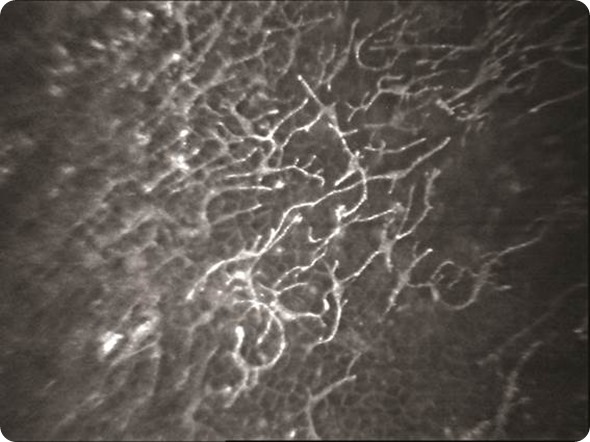

Dendritic cells cornea

Dendritic cells in the cornea imaged by confocal microscopy.